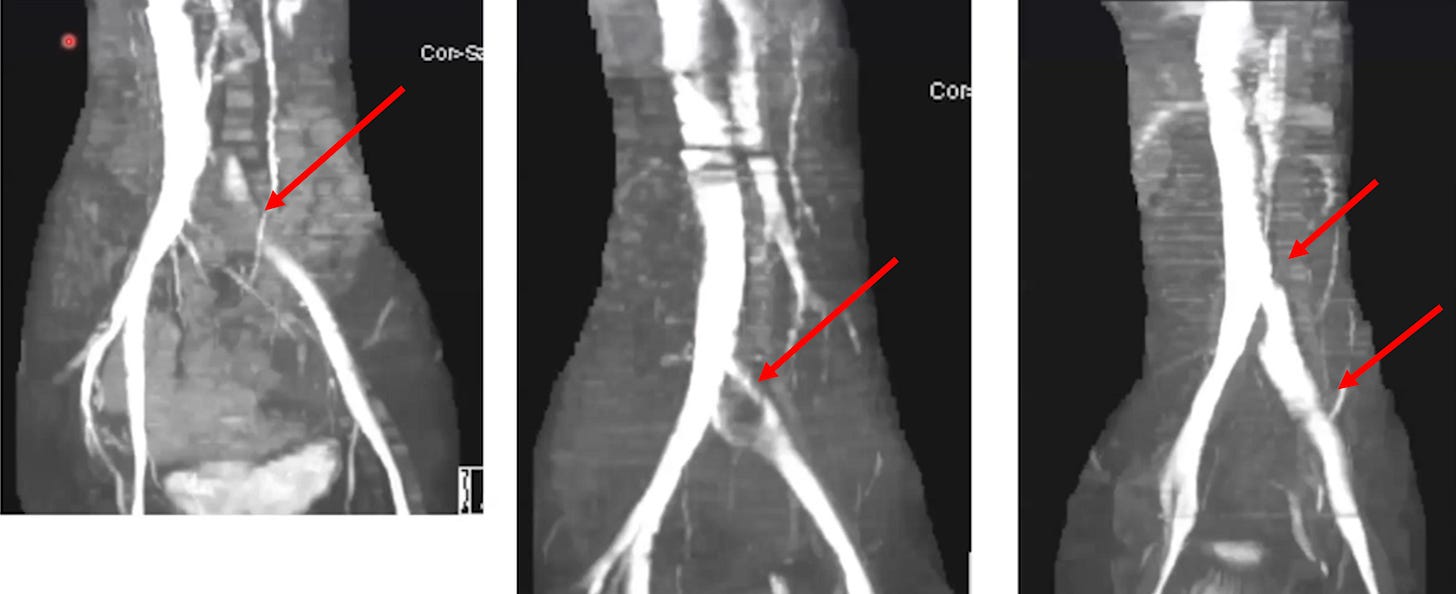

•A condition known as

May-Thurner syndrome affects slightly over

20% of the population. In it, the (high pressure) right common iliac artery overlies and compresses the (low pressure) left common iliac vein against the lumbar spine

Normally, individuals with this syndrome do not notice it, but it some cases it can predispose them to unexpected blood clots (due to venous return being obstructed).

•Dr. Vaughan believes that the (well-documented) damage

the spike protein causes to walls of the blood vessels weakens the iliac vein enough that pressure from the iliac artery can cause it to collapse. In turn, he has collected compelling radiography to prove it.

•If an iliac vein compression is treated with anticoagulation, this typically improves the symptoms of it, but once the anticoagulants are stopped, the symptoms return (as the source of the clotting has not been addressed). For this reason, iliac vein compressions are often treated with stenting, which Dr. Vaughan reports frequently significantly benefits patients.